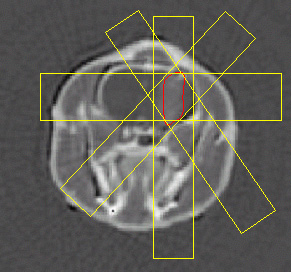

The rats were inoculated with glioma cells. On day 13 after the tumor inoculation, CDDP was injected intra-cerebrally at the tumor site and the irradiation is applied on day 14. The animals were set on a stereotactic frame rotating continuously on an axis orthogonal to the beam. The axis was positioned at the center of the tumor and the beam width adjusted to the tumor size. The irradiation geometry is shown on the figure below.